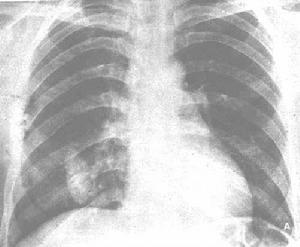

1.胸膜鈣化可為點狀、線狀、條狀、片狀或多數鈣化斑聚集成的斑塊狀,密度甚高,在CT片中其CT值通常為100HU以上。在大片增厚的胸膜影中的鈣鹽沉著多在近髒層胸膜處,且成條狀分布。如在側胸壁處的胸膜增厚並有鈣化,則在正位胸片中可見鈣化陰影與胸壁之間有一層軟組織影(即增厚的胸膜影)。

2.有的胸膜鈣化成套殼樣包在髒層胸膜的外面,與骨性胸廓間有一定的距離。

3.在胸壁包裹積液中的鈣化多為斑點狀且聚集成圓形或卵圓形,用不同的斜位檢查可顯示鈣化在胸膜面而不在肺野內。

4.塵肺中的胸膜鈣化常呈條狀或斑片狀,雙側性分布的多見。橫隔胸膜鈣化,為其特徵。